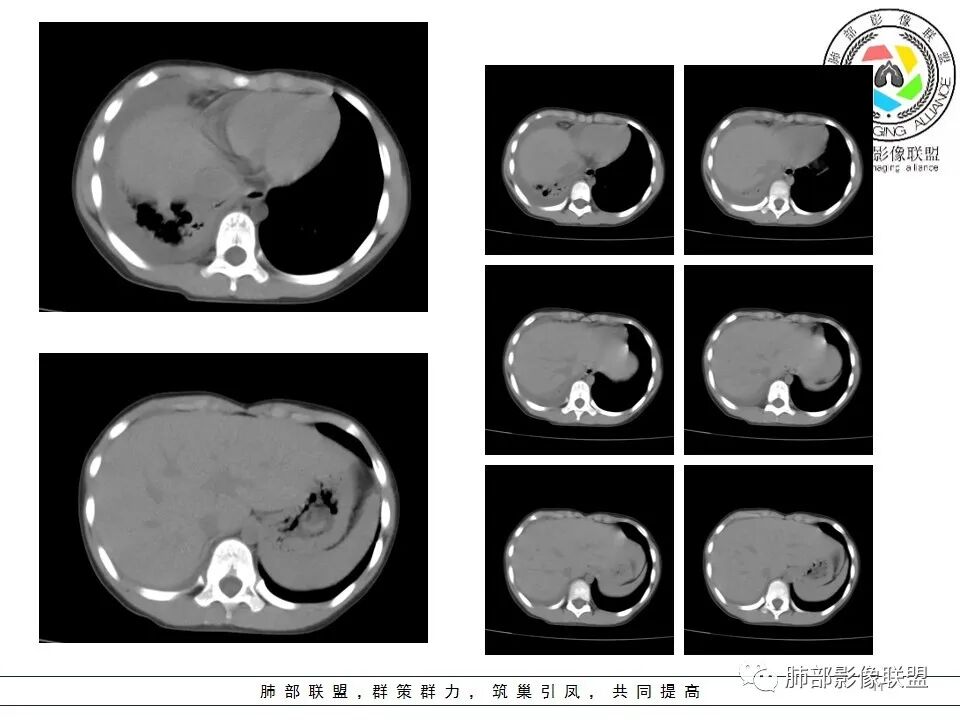

右前纵隔巨大软组织肿块,主要偏向右侧生长,边界不清,密度不均匀,内见大片状低密度坏死区及散在钙化灶,未见骨骼影及脂肪密度影。、双肺随机分布的转移瘤结节,右肺肺不张及右侧胸腔积液,提示恶性肿瘤病变伴双肺及胸膜转移。

前纵隔肿块常见的良性病变为畸胎瘤,恶性肿瘤有侵袭性胸腺瘤或胸腺癌、淋巴瘤、恶性生殖源性肿瘤、Askin(Pnet)瘤等。患儿9岁,30岁以下的胸腺肿瘤非常罕见。而且从病变密度不均,缺乏多结节堆积感,可见钙化等淋巴瘤的可能性不大。虽然这个病例缺乏增强及相关实验室检查,小儿前纵隔恶性肿瘤中恶性生殖细胞肿瘤相对常见,须鉴别的是Askin(Pnet)瘤,可结合有关HCG,AFP和LDH实验室检查帮助甄别。

是高度恶性生殖细胞肿瘤,卵黄囊细胞是唯一产生AFP的细胞,所以AFP升高是卵黄囊瘤或含有卵黄囊成份的生殖细胞肿瘤最重要的特征,其中卵黄囊瘤一般大于1000ug/L;影像表现肿块体积往往较大,易坏死囊变,易侵犯周围结构及转移。